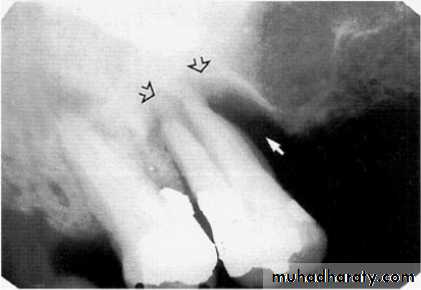

2.Vertical bone loss:- when there is greater bone loss in one tooth than on the adjacent tooth, so the bone level is not parallel with a line joining the CEJ.

Detection of periodontal disease

Vertical osseous defects can be divided into two primary types: Interproximal crater is a two-walled, trough like depression

that forms in the crest of the interdental bone between adjacent teeth.

The Infrabony defect is a vertical deformity within bone that extends apically along the root from the alveolar crest.

Types of infrabony defect (to design the treatment plan) :

Three-walled :surrounded by three bony walls.

Two-walled when both buccal and lingual cortical plates remain.

One-walled when one of these plates has been resorbed .

Often infrabony defects are difficult or impossible to recognize on a radiograph because one or both of the cortical bony plates remain superimposed with the defect.

Clinical and surgical inspections are the best means of determining the number of remaining

bony walls.